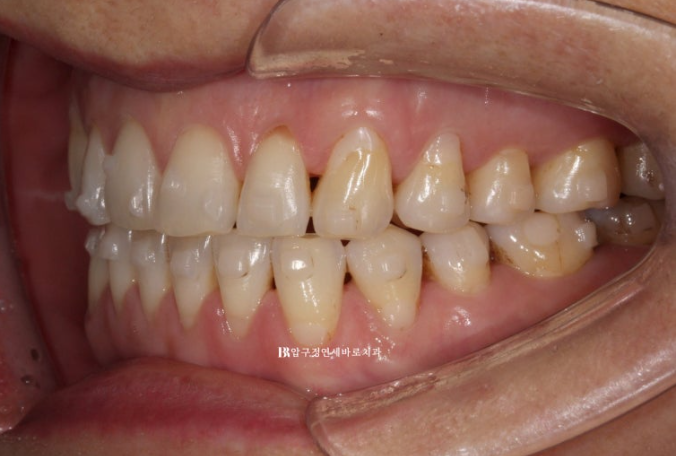

걱정하시는 교합도 잘 마무리 되었습니다.

추가장치의 목적은 미세하게 안 맞는 중심선을 맞추고 교정 후 어느정도 재발될 것을 예상해서 살짝 과개교합 상태를 만들어 놓는 것입니다.

아마 추가장치로 3개월 정도면 마무리 될 듯 합니다.

1차세트 7개월 소요되었고 추가장치 3개월이 걸린다면 총 치료기간은 10개월입니다.

클리피씨로 해도 이정도의 개방교합이 과연 10개월만에 완벽히 개선이 되었을까? 싶을 정도로

인비절라인으로 합입교정은 잘됩니다.

마지막으로 7개월간 변화 모습을 보여드리면서 마무리 하겠습니다.